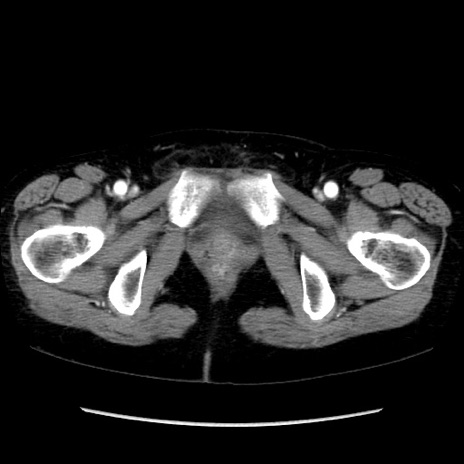

症例32(横断像)

【症例】40歳代 女性

【主訴】上腹部痛、嘔気・嘔吐

【現病歴】約9時間前頃から急に上腹部痛、嘔気、嘔吐が出現。改善しないため救急要請。

【既往歴】子宮頚癌(広汎子宮全摘術、放射線療法)、腸閉塞

【身体所見】腹部:平坦、軟、腸雑音亢進、上腹部を中心に腹部全体に圧痛あり。

【データ】WBC 8400、CRP 0.03